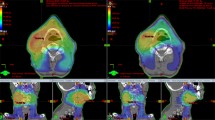

All patients underwent CT imaging in the supine position with a custom thermoplastic immobilization cast. Constant bowel and bladder filling protocols were followed at the time of the procedure. CT images were acquired with a 3 mm slice thickness and were transferred to the treatment planning system. Clinical target volumes (CTVs) were contoured as CTV nodal (CTV 1) and CTV primary (CTV 2 and 3) (Bansal et al. 2013). CTV 1 included involved nodes and relevant draining nodal groups (common iliac, internal iliac, external iliac, obturator, and presacral). CTV 2 included the uterine corpus, the entire cervix, and the vagina depending upon the vaginal involvement, whereas CTV 3 encompassed the parametrium. Appropriate internal target volume (ITV) and planning target volume (PTV) margins were generated. Additionally, para-aortic LN CTV was contoured according to the guidelines by Keenan et al. for delineation of para-aortic lymph node region in cervical cancer (Keenan et al. 2018). Positron emission tomography (PET) avid LNs were contoured with a 1-centimeter isotropic expansion to generate boost volumes. Dose constraints for targets and OARs were given as per the EMBRACE II protocol (Potter et al. 2018). Two sets of plans were generated for each patient - SIB-VMAT and SEQ-VMAT.

For the SIB plans, the prescribed dose was 50.4 Gy to the pelvis (primary tumour, uterus, and the parametrium and elective nodal volume) and 58.8 Gy to the FDG-avid nodes. These doses were delivered in 28 fractions over 5.6 weeks. For the SEQ-VMAT plans, the prescribed dose was 50.4 Gy to the pelvis in 28 fractions (primary tumour, uterus, and the parametrium) followed by a boost of 9 Gy in five fractions to the involved LN. Plans were optimized to achieve adequate target coverage with maximal sparing of the OARs.

The dosimetric analysis compared two EBRT techniques, SIB-VMAT and SEQ-VMAT, for ten patients of cervical cancer with involved LN in terms of target coverage, OARs sparing, and radiobiology. The patient and treatment characteristics are shown in Table 2. The comparison of the two techniques showed that SIB-VMAT exhibited superior target coverage compared to SEQ-VMAT although both techniques achieved the pre-specified target volume coverage. Specifically, SIB-VMAT plans achieved significantly higher mean percentages of the PTV receiving at least 95% prescribed dose (V95) and gross tumour volume receiving at least 100% (V100) of the prescribed dose. SIB-VMAT plans also demonstrated significantly better dose conformity over SEQ-VMAT plans. In contrast, the HI was better for SEQ-VMAT as compared to SIB-VMAT (0.09 vs. 0.19, p < 0.01). Table 3 shows the comparison of the two planning techniques in terms of planning targets achieved.

While analyzing all ten patients together, SIB-VMAT was observed to have been superior to SEQ-VMAT in terms of doses achieved in PTV V95 (99.4% vs. 98.9%, p = 0.03) and GTV V100 (99.7% vs. 98.2%, p = 0.01) with lesser areas of high dose region in PTV i.e., V110 (19.5 vs. 33.3%, p < 0.01) along with a better CI (Table 3). In contrast to these findings, a significantly better homogeneity index was attained with SEQ-VMAT planning (0.19 vs. 0.09, p < 0.01; Table 3). A plausible explanation for this finding could be the overlap of dose distributions from the plans of two sequential phases when the HI was being calculated for the plan sum in SEQ-VMAT plans. In plan sum, average dose distributions of two plans were observed where the presence of hot spots and cold spots changed the final dose distribution resulting in a more homogeneous dose as compared to SIB plans.